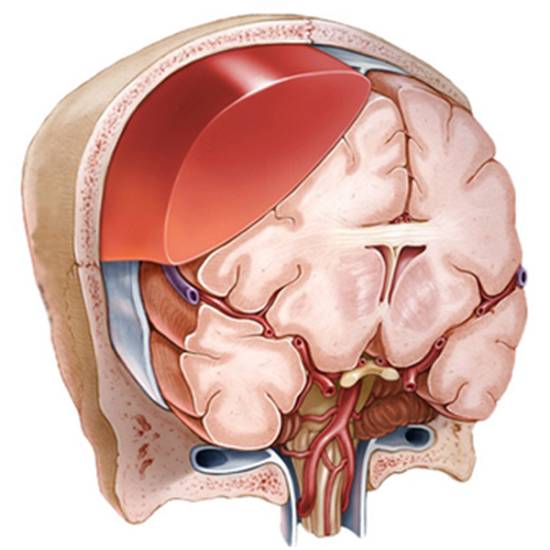

• Эпидуральная гематома — обычно возникает после травматических повреждений. Локализуется под областью перелома, между костями черепа и твердой оболочкой мозга, визуально выглядит как двояковыпуклая линза.

Эпидуральной гематомой называют небольшое скопление крови, расположенное над поверхностной оболочкой мозга. Обычно она возникает при переломах черепа, когда источником кровотечения становятся оболочечные артерии. В зависимости от расположения относительно мозжечка, эпидуральная гематома делится на подвиды:

• Субтенториальная гематома — ниже намета мозжечка;

• Супратенториальная гематома — выше намета мозжечка.

Признаки эпидуральной гематомы на КТ

Эпидуральная гематома на томографических снимках имеет характерную форму, напоминающую двояковыпуклую линзу, которая соприкасается с костью. При переломе черепа может наблюдаться, что перелом находится в области дна гематомы.

Точный признак эпидуральной гематомы — наличие ликворных «стрелок» в углах, возникающих при разрыве арахноидальной оболочки. В этом случае ликвор переходит из арахноидальной полости в субдуральное пространство, а также могут быть видны костные отломки. Обычно структура эпидуральных гематом однородная. Неоднородное скопление крови или наличие газа в черепе встречаются крайне редко.